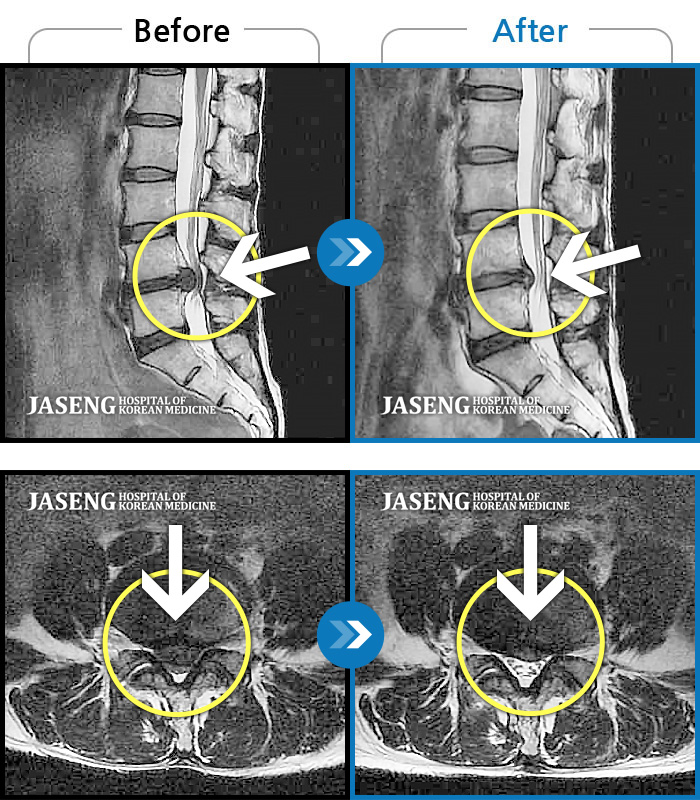

허리디스크

수원 · 김태성 원장

허리 통증과 좌측 대퇴부~종아리 저림과 통증

촬영시기

2011.03.14 ~ 2024.05.24

2024.11.21